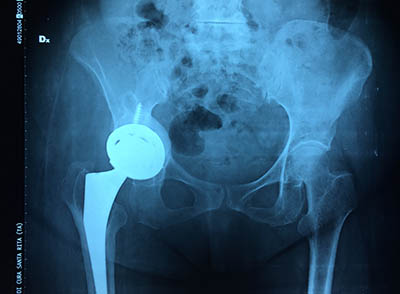

Quindi ho utilizzato dell’osso di banca tritato cercando di ricostruire il fondo rx post-operatoria artdell’acetabolo su cui ho fissato con 3 viti un cotile in tantalio che ha un altissimo potere di osteointegrazione. Lo stelo appariva ben integrato quindi decido di non cambiarlo.

Le radiografie di controllo sono state ottime sin da subito  come il decorso post operatorio della paziente che ha deambulato senza stampelle dopo 2 mesi dall’intervento.  E’ molto contenta ed è potuta tornare alle sue attività senza limitazione.